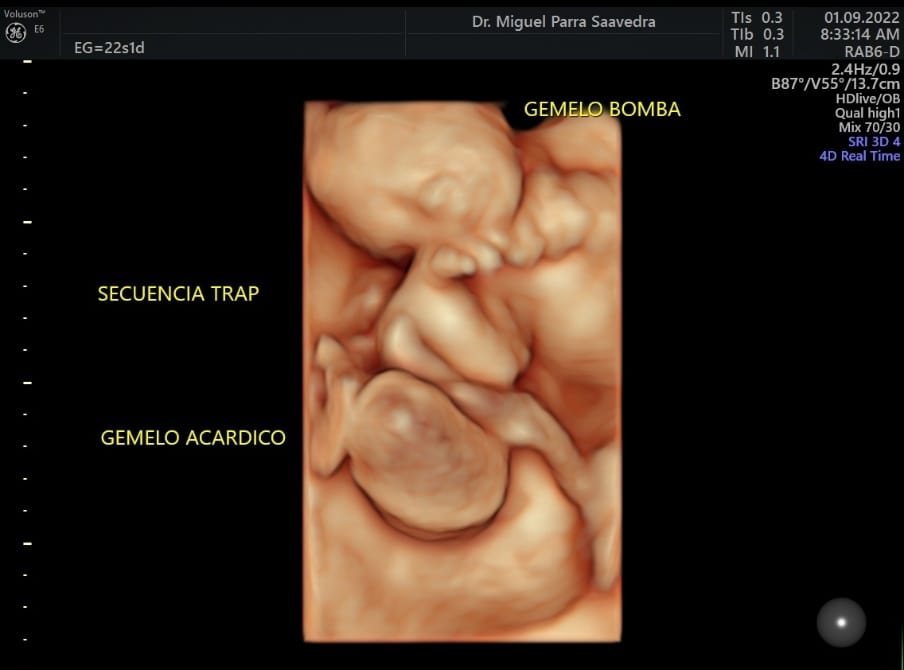

El caso, nada común, es conocido como secuencia trap. A la semana 17, en medio de un control prenatal, se detectó que Samuel crecía en el vientre de su madre unido a un gemelo acárdico, que apenas era una pierna. Dicha malformación puso en riesgo la vida del bebé sano (gemelo bomba) ya que le estaba causando una falla cardiaca. De no haber sido intervenido y separado, habría fallecido.

La secuencia de perfusión arterial revertida de gemelos o TRAP (del inglés ‘Twin Reversed Arterial Prefusion’) es una condición que ocurre en gemelos que comparten una sola placenta (monocorial), en la cual existe un gemelo con malformaciones severas (el gemelo acárdico) que lo hacen incompatible con la vida.

“Samuel nació a término, a las 37 semanas y en perfectas condiciones después de nuestra cirugía fetal, con la cual logramos separarlo de su gemelo acárdico de una sola pierna. Samuel desarrolló corazón, pero su gemelo Daniel tan solo desarrolló una pierna y se alimentaba de la sangre de su hermano. En estas condiciones tuvimos que hacer una cirugía láser para llegar hasta la cavidad uterina y coagular la circulación de Daniel, el bebé trap que no tenía corazón, para que Samuel pudiese sobrevivir”, expresó el Dr. Miguel Parra.